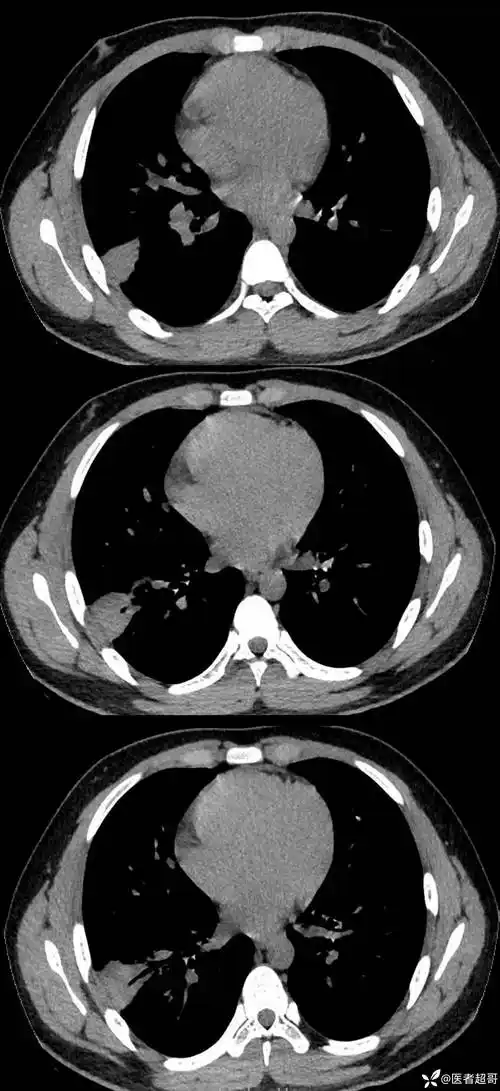

双肺下叶高密度伴充气支气管征象请分析